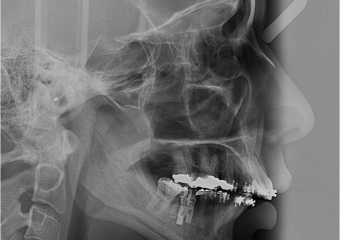

Telerradiografia inicial